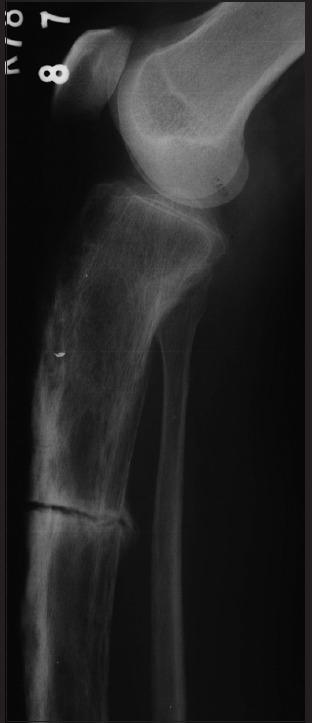

Mimics of bone tumors.